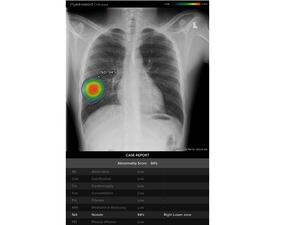

جنرال إلكتريك للرعاية الصحية تواصل تقديم التكنولوجيا المبتكرة لدعم المتخصصين في الرعاية السريرية في عالم يشهد تفشي وباء "كوفيد-19" اليوم

22 يونيو 2020 - 11:52 GMT

جنرال إلكتريك للرعاية الصحية تطلق منظومة جديدة مدعومة بالذكاء الاصطناعي لرصد النتائج غير الطبيعية في الصور الشعاعية